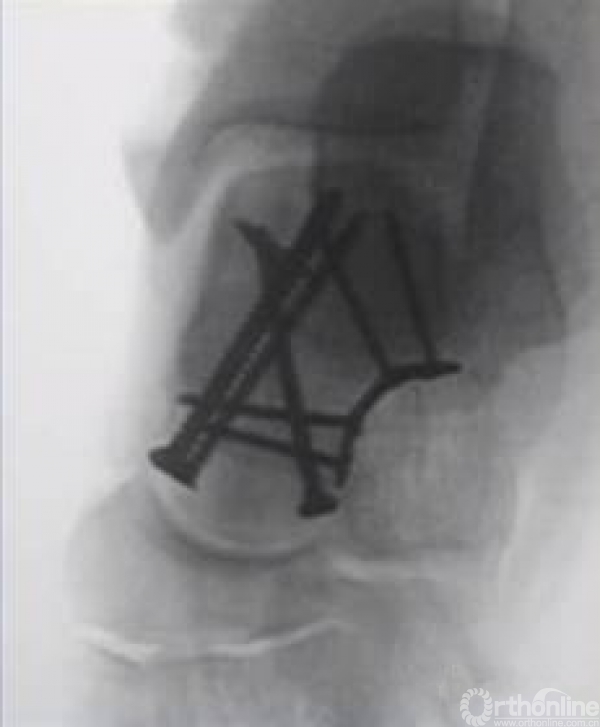

如果一侧钢板的位置不佳,则容易造成另外一侧的骨折裂开。所以最好的固定是一侧用钢板固定,另外一侧可采用螺钉进行加压,对于颈部的骨折,避免另外一侧开口。